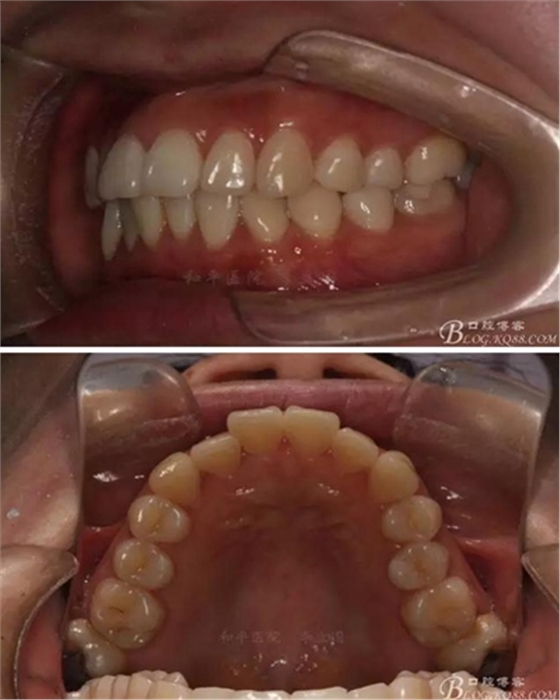

患者,女,主訴:牙齒不齊。

如圖,該病例為簡單排齊病例,但77鎖合是矯治中的關(guān)鍵所在,你會怎么處理?